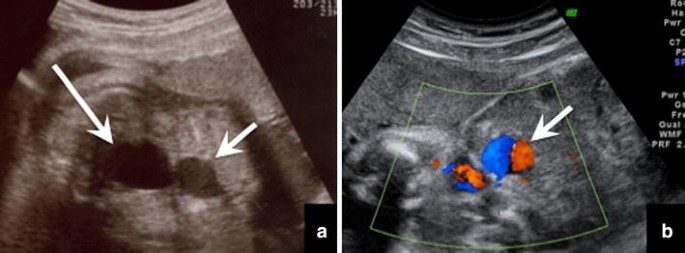

Medical News Radiology Mcqs For Usmle Aipgee And Plab Double Bubble Sign Causes Include A Congenital Obstruction Duodenal Web Duodenal Atresia Duodenal Stenosis Annular Pancreas B

シングルバブル、ダブルバブル、トリプルバブルサインの違い なになにバブルサインとは、消化管が閉鎖される疾患のレントゲン所見のこと。 シングルバブルサイン ダブルバブルサイン トリプルバブルサイン 画像 出典 出典:105D41 出典スクリーン ダブルバブル クリア honda vtr1000f '97 〜 '05 カラー:クリア タイプ:ダブルバブル ご注意 写真は実際の製品と異なる場合がございます。 16年3月22日からの新価格です。Double(ダブル)は、日本の女性 歌手、ソングライター、takakoによるソロ・プロジェクト。 姉妹デュオとして1998年にデビューしたが、1999年に姉のsachikoが急逝したため、以降は現在の形態となった。 06年からはdj lilly aka double(ディージェイ・リリー・エーケーエー・ダブル)名義

bubble バブル の値段はいくら? 今回はTWICEの画面で紹介するけど bubble バブル のアプリから値段を確認できるよ。 ここで注意したいのが、bubbleの登録はNiziUメンバー1人の値段ね。でも複数メンバー登録すると割引もあるよ。ダブルバブルサイン 上部消化管閉塞 十二指腸閉塞 ダブルマドックス杆検査 上部消化管閉塞 先天性消化管異常 メルクマニュアル18版 日本語版 特徴的徴候は,唾液過多,哺乳を試みた後の咳嗽とチアノーゼ,嚥下性肺炎である。 食道 遠 ★リンク